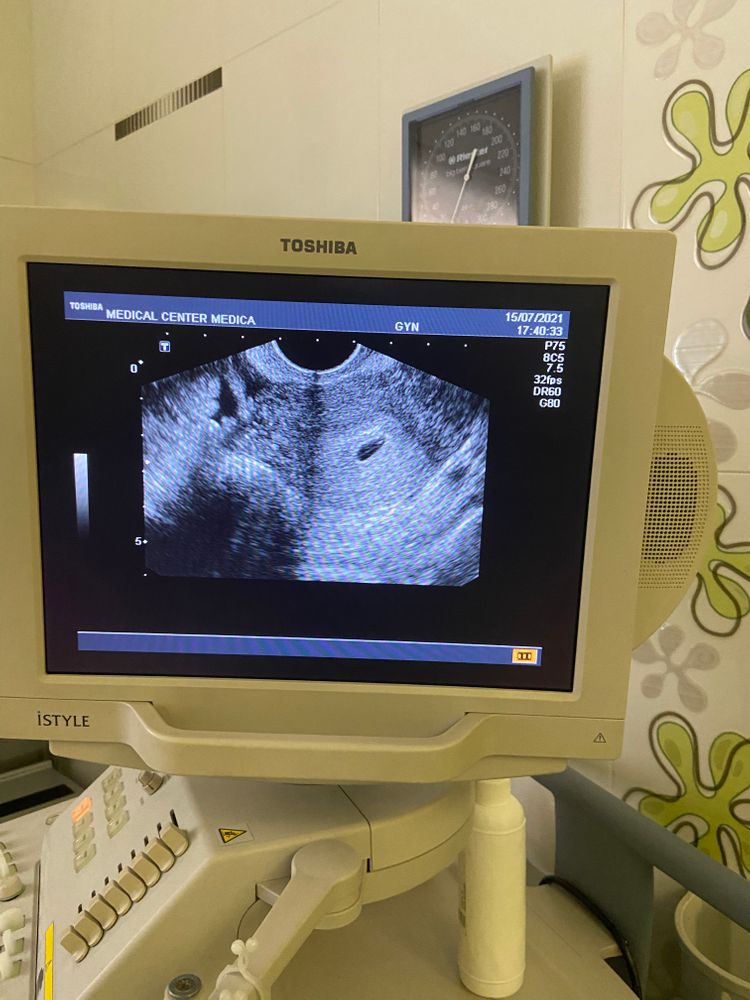

Не видно эмбрион на УЗИ

Изображение

Всем привет! Подскажите, пожалуйста, 22 дпо, 1 неделя задержки (гестационный срок 3 недели), пришла к своему доктору, сделали УЗИ, плодное яйцо 8 мм, желтое тело 24 мм, а эмбрион не увидела. Сказа